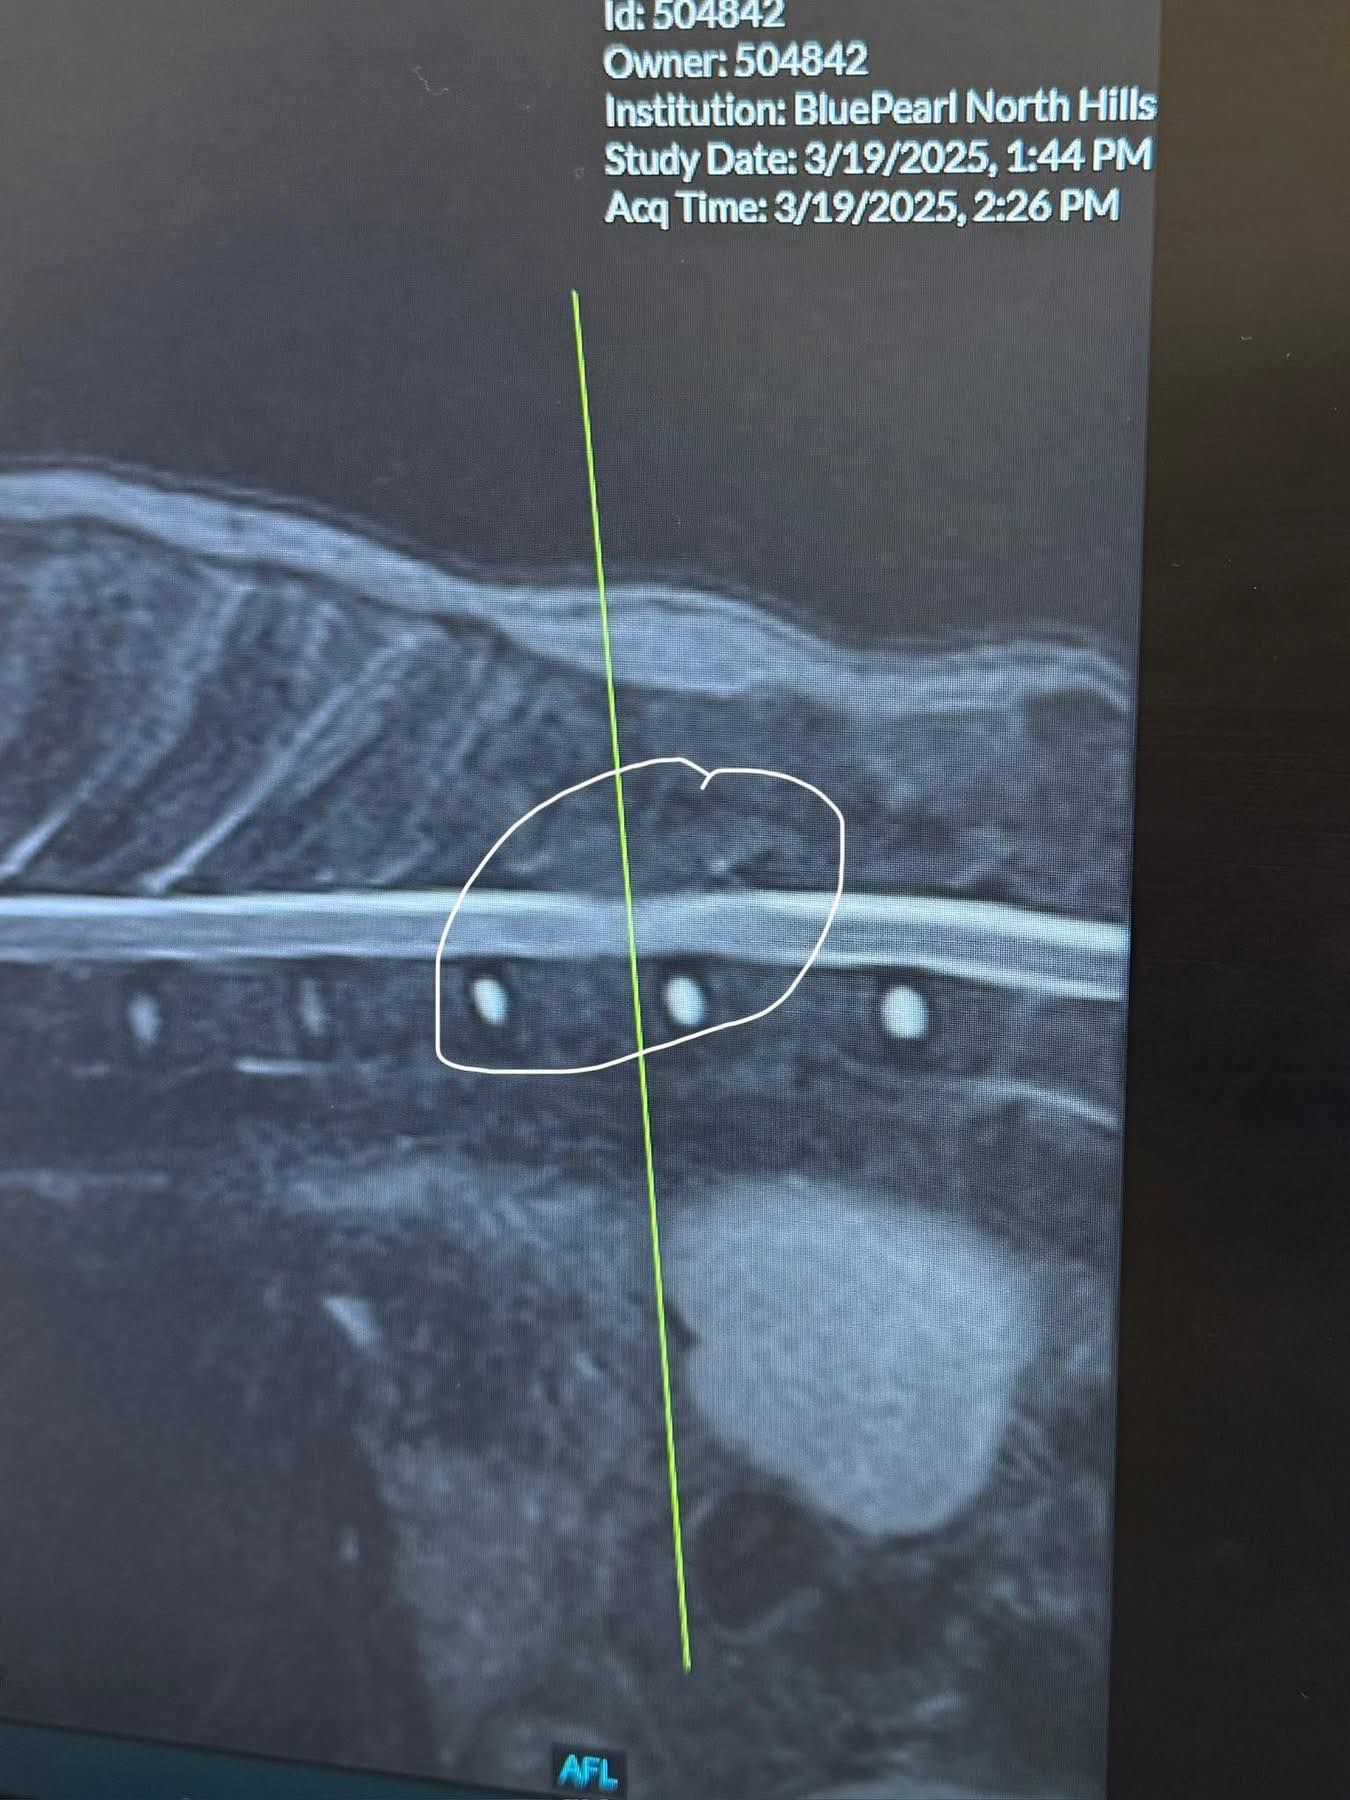

Clover has a tumor around her spinal cord, between T11 & T12 vertebrae. Basically right in the middle of her spine. In the MRI photos below, the third photo shows normal spinal cord looking at it as though you sliced into a pumpkin roll. The fourth photo shows the area the tumor is compressing on her spine. The fifth photo is the tumor itself.